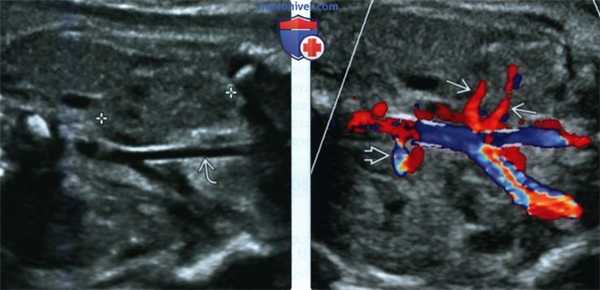

(Слева) В 29 нед. обнаружена правая эктопическая почка (калиперы) вблизи правой общей подвздошной артерии Левая почка расположена нормально (не показана).

(Справа) Для обнаружения тазовой почки при пустом почечном ложе прибегают к ЦДК. В данном случае левая почечная артерия расположена нормально, а от аорты вблизи бифуркации отходят две правые почечные артерии.